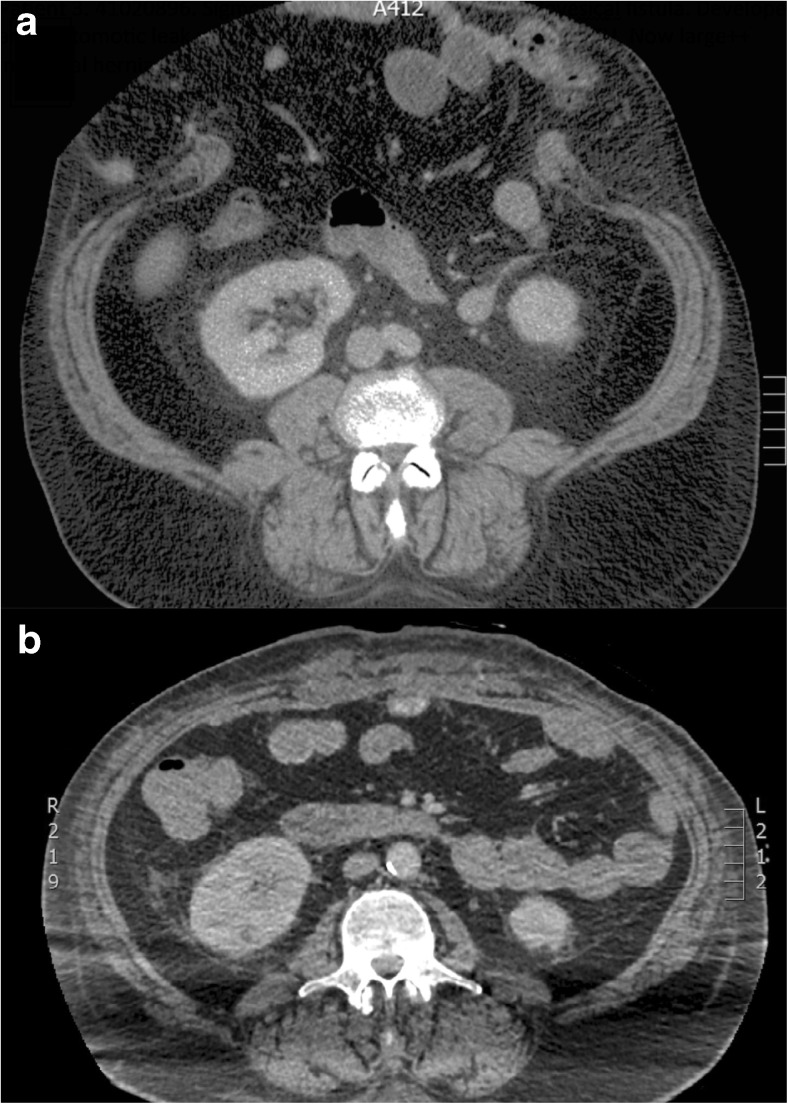

Preoperative CT will indicate the precise location of the hernia and provides prognostic information regarding the scale of subsequent surgery [20]; for example, smaller hernias may be closed using mesh alone (Fig. 5) whereas larger defects will need additional component separation (Fig. 6). Clinical examination by the surgeon will usually provide extensive information regarding precise anatomical site but imaging may provide unexpected information. Hernia extent on CT will also help indicate the scale of subsequent abdominal and cardiovascular insult (fluid loss is considerable during extensive CVH repair), so that appropriate preoperative conditioning, intraoperative support and postoperative care can be scheduled. Ultimately, by imaging the true extent of the hernia, CT is able to indicate which can be dealt with by “general” surgeons and which need attention from a CVH specialist.

Fig. 5.

a Preoperative axial CT showing a ventral hernia containing small bowel. b Postoperative axial CT showing ventral hernia repair achieved by apposition of the rectus muscles in the midline combined with an intraperitoneal mesh

Fig. 6.

a Preoperative axial CT showing a huge ventral hernia following sigmoid colectomy. b Postoperative axial CT showing ventral hernia repair achieved by bilateral anterior component separation combined with an intraperitoneal mesh